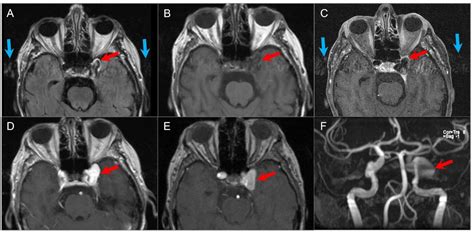

MRI (Magnetic Resonance Imaging) Provides high-resolution images of soft tissues, nerves, and the brain.

CT Scan (Computed Tomography) Highly effective at highlighting bony structures and identifying tumor-related bone erosion.